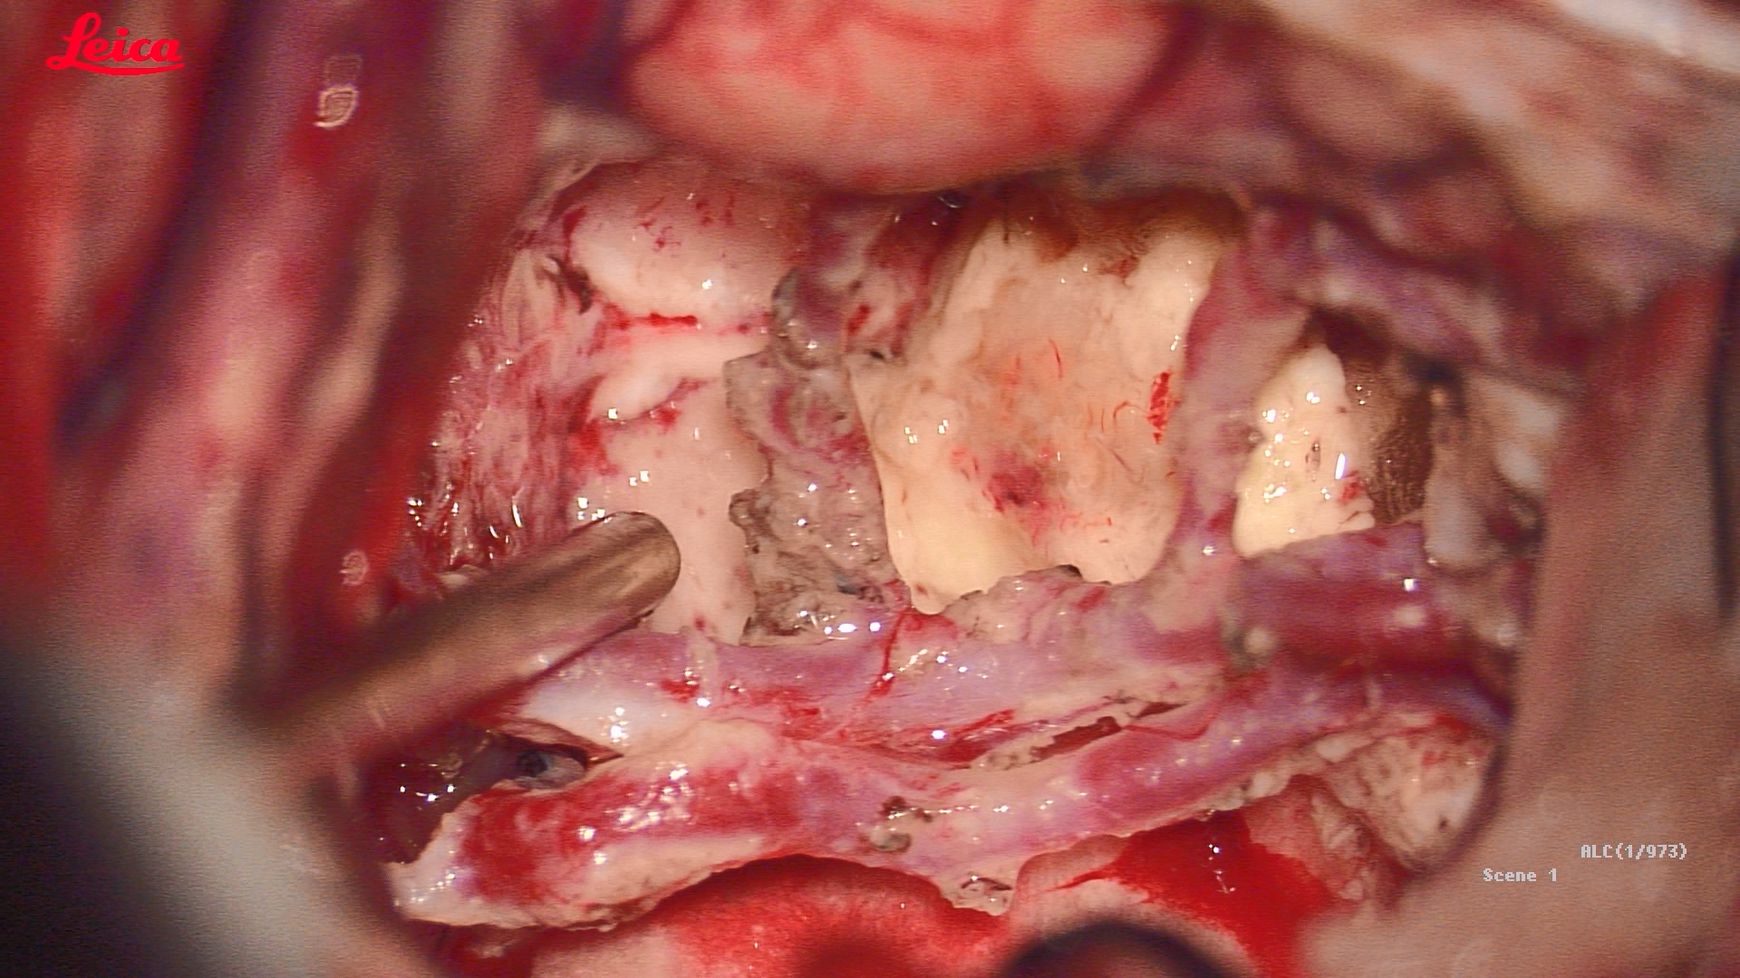

巨大蝴蝶型胶质母细胞瘤(Butterfly glioblastomas)切除术

患者,女性,58岁,因“反应迟钝、记忆力下降1月,加重伴头痛、恶心、呕吐1周”入院。

术后第二天,患者症状显著改善,认知功能明显好转

术后半月恢复正常生活